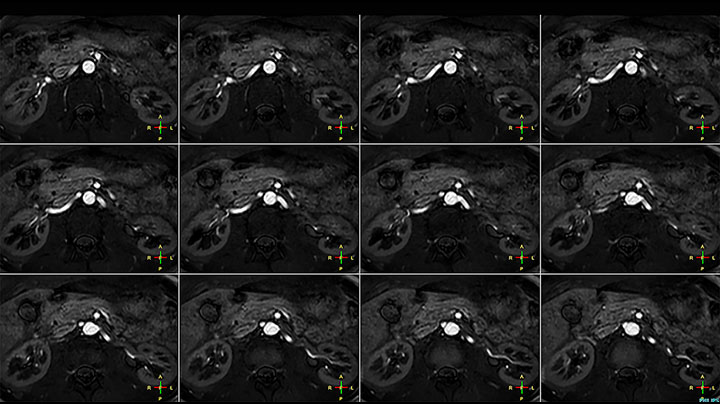

MRI of Pancoast tumor

Although the area between the neck and the top of the lung is one of the most difficult areas for MRI, Prodiva 1.5T images show good quality in this 56-year-old male with Pancoast tumor on the right. mDIXON TFE images shows excellent fat suppression in the neck area and the DWI shows almost no distortion.